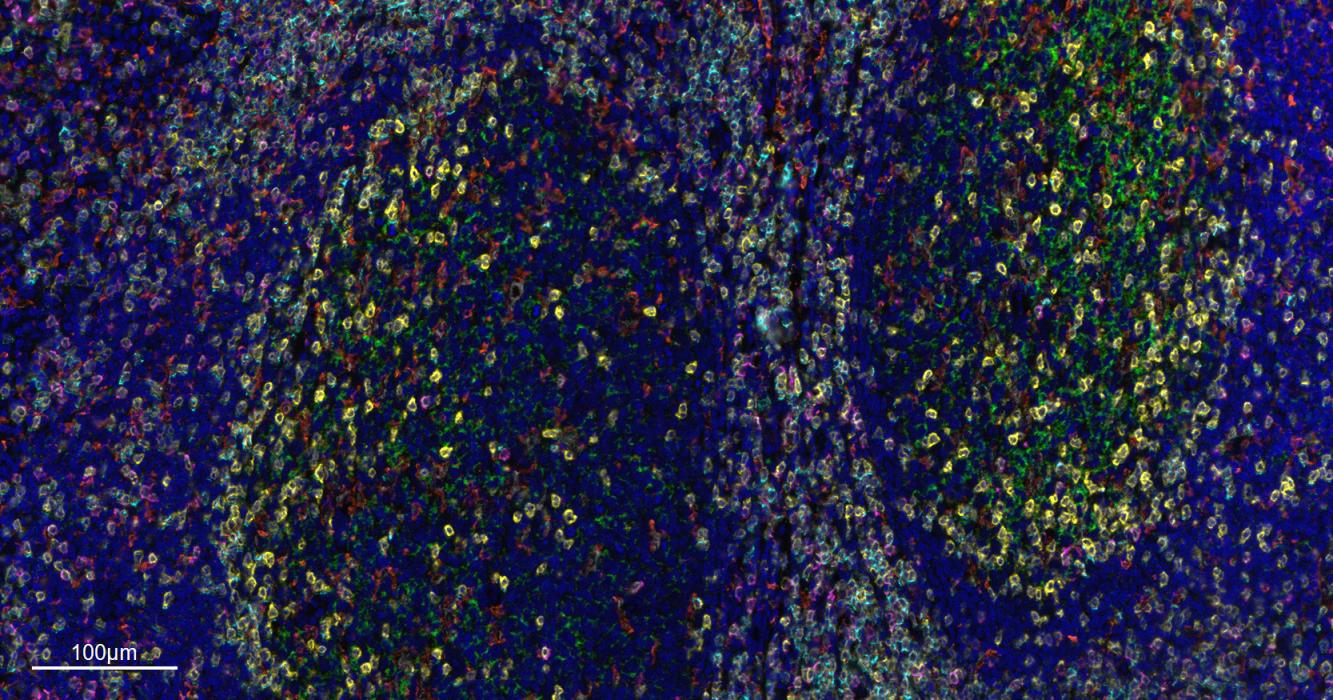

Paraformaldehyde-fixed, paraffin embedded Human Tonsil. Merged staining of anti-CD8A (bsm-34251M; 1:200; pink) anti-CD4 (bsm-52469R; 1:200; light blue) anti-CD3E (bsm-60002R; 1:200; green) anti-CD68 (bsm-60634R; 1:200; white) anti-CD11c (bsm-61135R; 1:200; orange) and anti-CD20 (bsm-63327R; 1:200; yellow) DAPI (dark blue) was used as a nuclear counter stain.

Paraformaldehyde-fixed, paraffin embedded Human Tonsil. Merged staining of anti-CD68 (bsm-60634R; 1:200; red) anti- CD20 (bsm-63327R; 1:200; white) anti-CD3E (bsm-60002R; 1:200; light blue) anti-CD4 (bsm-52469R; 1:200; rose red) anti-Ki67 (bsm-52455R; 1:200; bean green) anti-Vimentin (bsm-33170M; 1:200; yellow) and anti-Pan Cytokeratin (bsm-34137M; 1:150; green) DAPI (dark blue) was used as a nuclear counter stain.